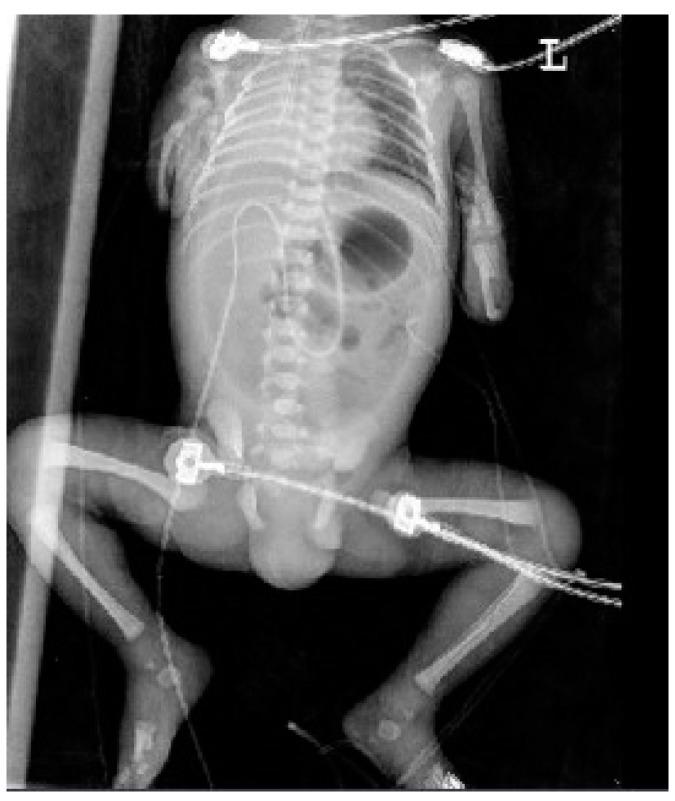

: VACTERL association is a widely known congenital malformation that includes vertebral, anal, cardiac, tracheoesophageal, renal, and limb anomalies. Patients with VACTERL and hydrocephalus appear to form a distinct group, both genetically and phenotypically, and their condition has been called VACTERL-H syndrome. Most cases of VACTERL-H have been reported postnatally, as VACTER-H syndrome is difficult to diagnose prenatally. Here, we report a case of VACTERL-H syndrome in a dichorionic and diamniotic twin diagnosed prenatally by ultrasonography and confirmed postnatally by three-dimensional computed tomography (3D CT). A 34-year-old multiparous female was referred to our institution at 31 + 3 weeks gestation for suspected fetal ventriculomegaly. Detailed examinations using two-dimensional and Doppler ultrasounds revealed hydrocephalus, bilateral dysplastic upper arms, radial aplasia, unilateral pulmonary agenesis, dextrocardia with right atrial enlargement, a unilateral hypoplastic ectopic kidney, a single umbilical artery, a tracheoesophageal fistula with a small stomach, polyhydramnios, and anal atresia. Findings from the postnatal 3D CT aligned with the prenatal diagnosis, showing upper-limb agenesis, dextrocardia with pulmonary hypoplasia, tracheoesophageal fistula, imperforate anus, and colon dilatation. The affected 1390-g male twin had an unaffected 1890-g female twin sister and a healthy 6-year-old brother. : Upon encountering fetuses with multiple anomalies, including ventriculomegaly, a small stomach with polyhydramnios, an abnormally positioned heart, and upper-limb abnormalities, clinicians should perform systematic ultrasonographic examinations to detect associated anomalies and be aware of VACTERL-H syndrome.

VACTERL 协会是一种广为人知的先天性畸形,包括脊柱、肛门、心脏、气管食管、肾脏和肢体异常。患有 VACTERL 和脑积水的患者似乎在遗传和表型上形成了一个独特的群体,他们的病情被称为 VACTERL-H 综合征。大多数 VACTERL-H 病例都是在产后报告的,因为 VACTERL-H 综合征很难在产前诊断。在这里,我们报告了一例产前通过超声诊断并通过三维 CT 产后证实的双绒毛膜和双羊膜性双胞胎 VACTERL-H 综合征病例。一位 34 岁的多产妇在 31+3 周妊娠时因疑似胎儿脑室扩大被转诊至我们机构。使用二维和多普勒超声进行的详细检查显示脑积水、双侧发育不良的上臂、桡骨发育不全、单侧肺发育不全、右心房扩大的右位心、单侧发育不良的异位肾、单脐动脉、伴有小胃的气管食管瘘、羊水过多和肛门闭锁。产后的 3D CT 检查结果与产前诊断一致,显示上肢发育不全、肺发育不全的右位心、气管食管瘘、肛门闭锁和结肠扩张。受影响的 1390 克男性双胞胎有一个未受影响的 1890 克女性双胞胎妹妹和一个健康的 6 岁弟弟。